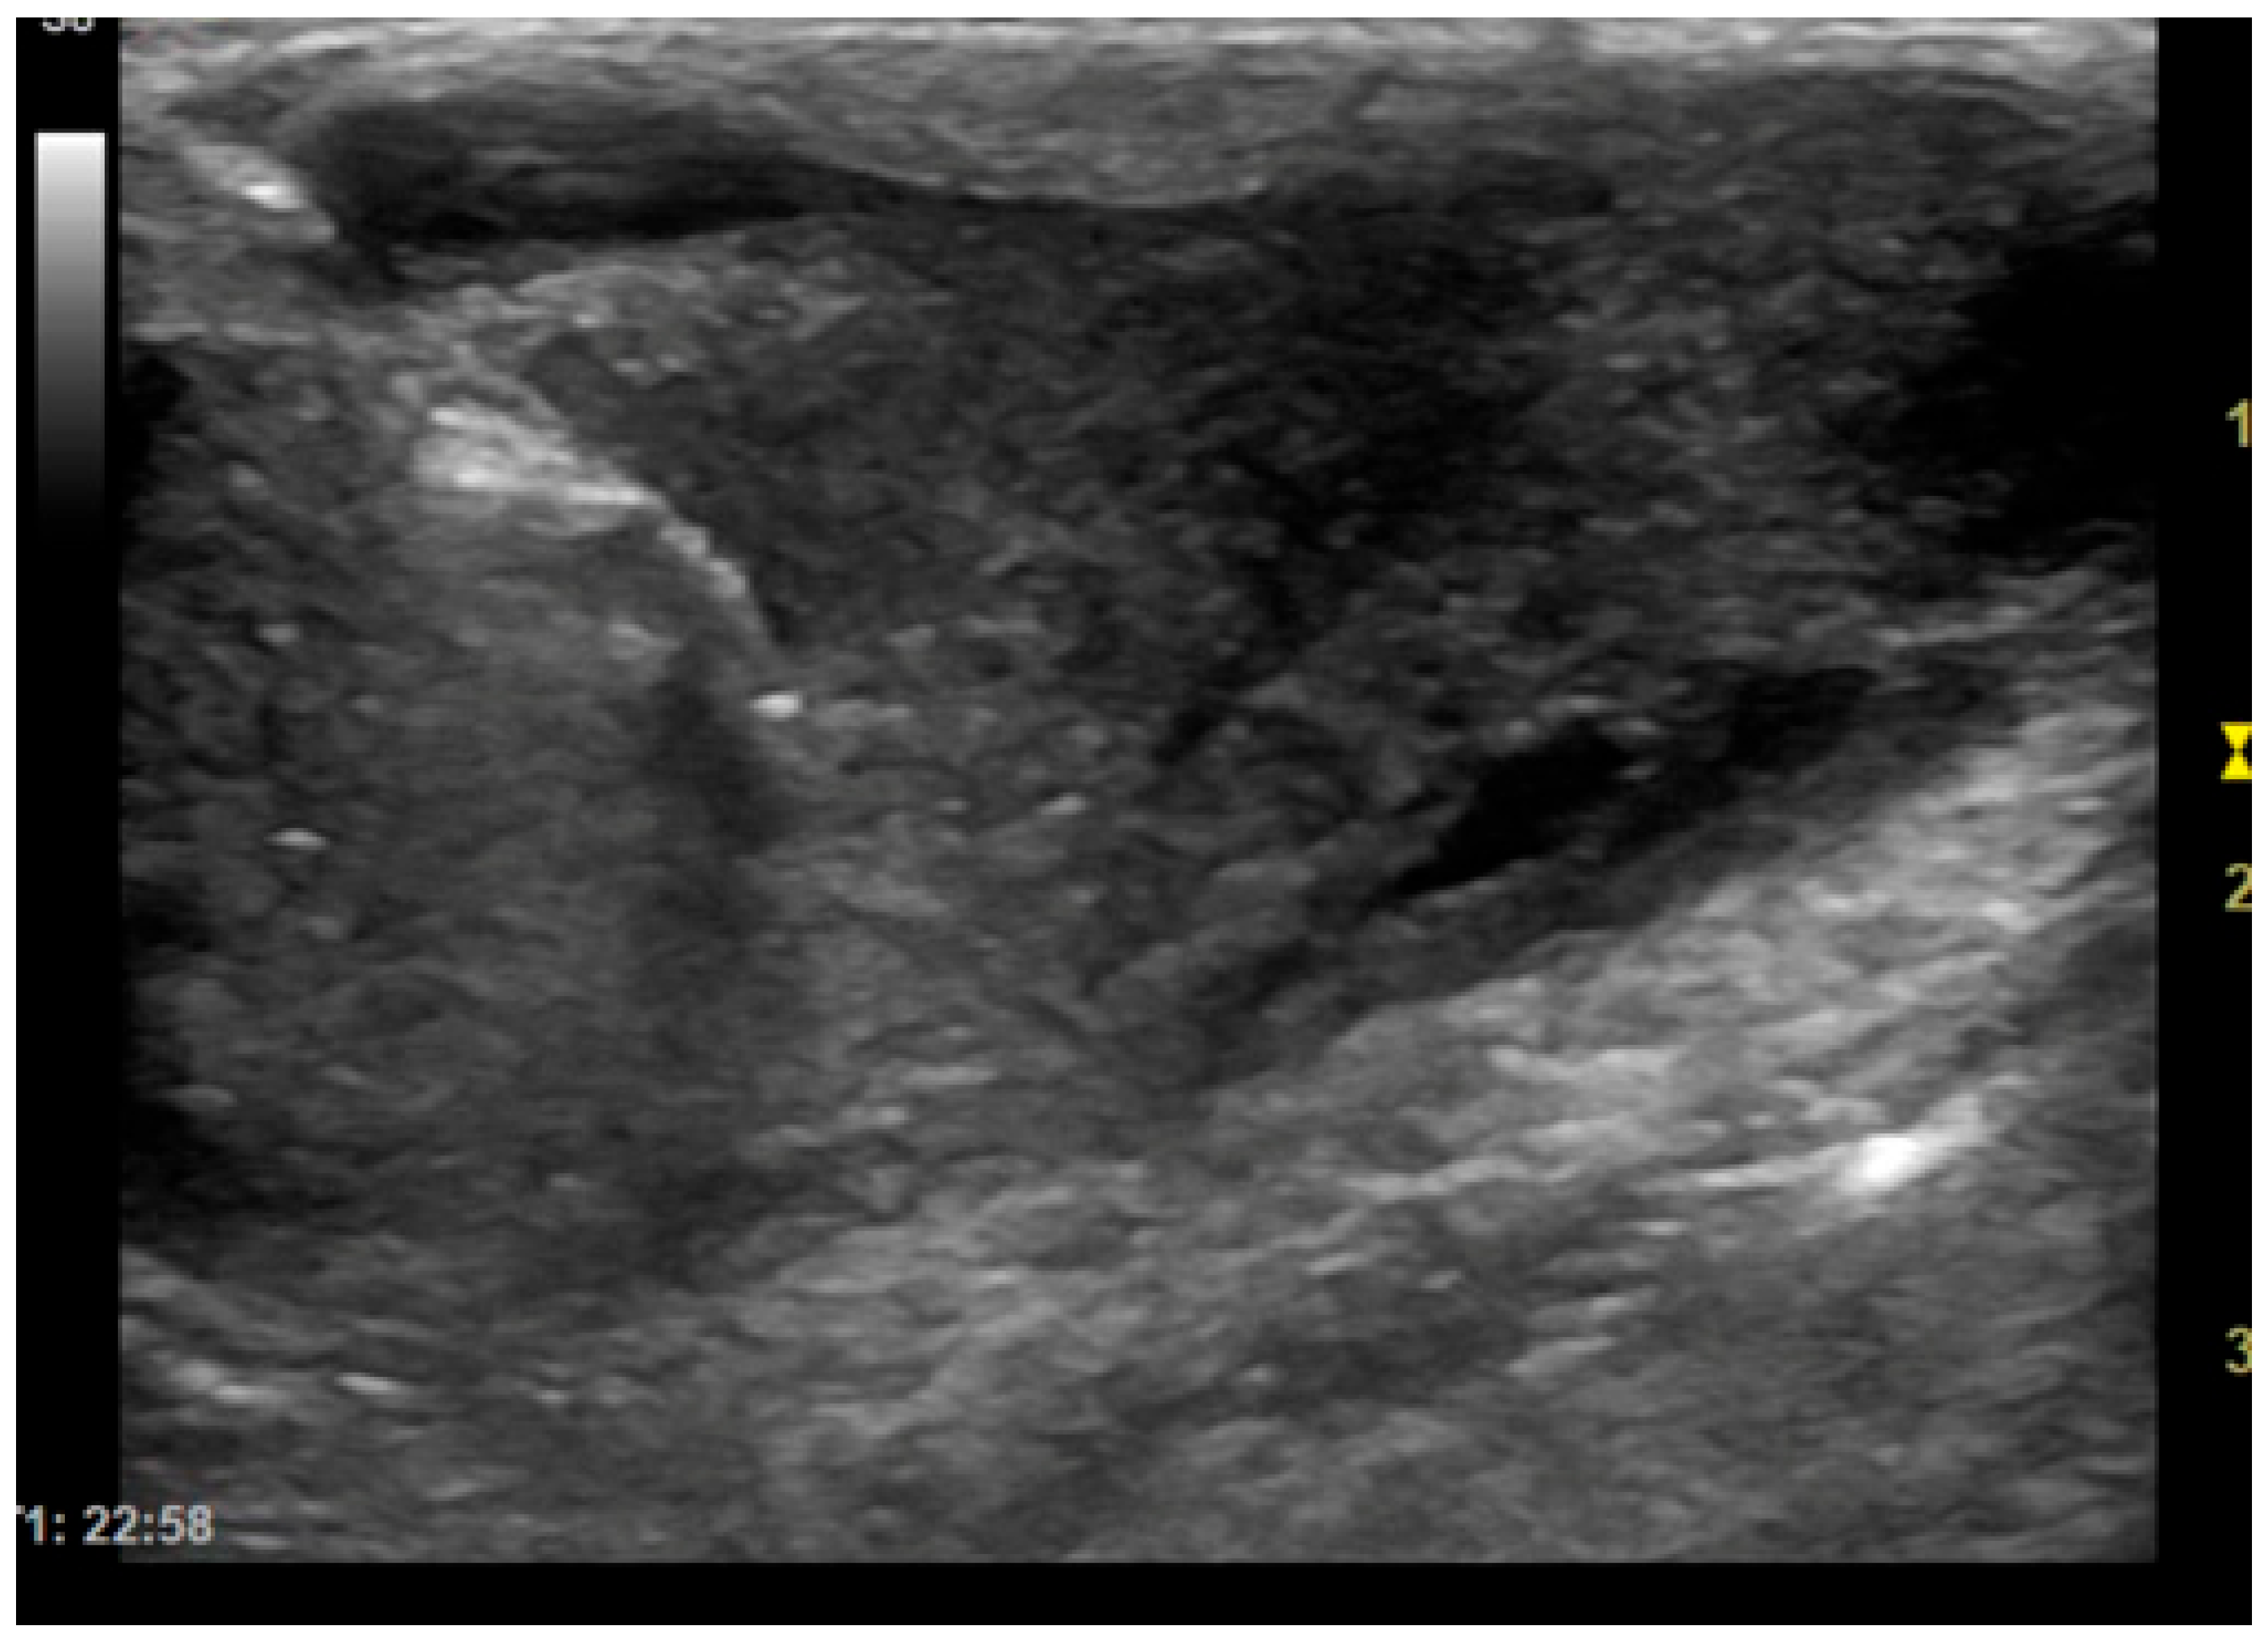

ROSE provides immediate feedback on sample adequacy, enabling a faster and more reliable diagnosis [10]. To increase the likelihood of obtaining diagnostic samples, multiple biopsies are usually performed on the same lesion. However, performing each biopsy, especially in dangerous anatomical locations, can cause complications. Therefore, the main objective of this study is to try to reduce the number of biopsies that need to be performed to obtain a diagnostic sample, thereby also lowering the risks for the animal. Analysis of the results of this study has shown that extemporaneous cytological examination can be useful for the purpose described above. In fact, out of 79 biopsies collected, extemporaneous cytological examination revealed cellularity in 81% of cases. The presence of representative cellularity in these samples made it possible to terminate the biopsy procedures. In the remaining cases, the lack of cellularity in the extemporaneous cytology suggested that further sampling should be carried out. Furthermore, it should be noted that in most of the samples in which no cellularity representative of the biopsied lesion was detected (25 out of 79), the cause was attributed to poorly stained and/or poorly fixed slides (technical problems), the presence of blood-contamination and poor cellularity due to the intrinsic nature of the sampled lesion. During the oncogenic process, blood may not arrive in sufficient quantities, causing an environment that is poor in oxygen (hypoxic) and nutrients (ischemic), which leads to necrosis, thus reducing the cellularity of the sample [13,14]. Furthermore, it is important to note that the interventional procedures in this study, excluding those performed with CT, were performed with 2D-mode ultrasound as shown in Figure 3. CT-guided biopsy sampling is, in fact, a procedure mainly indicated for bone lesions or lesions located in areas not easily accessible with US [6,15]. The relevance of this has been demonstrated in several studies reported in the literature as it can lead to several advantages. In the study by Vignoli et al. [16], in 2013, the importance of CT and guided biopsy in the staging of cancer patients was emphasized. In fact, although rare, muscular metastases can occur with different types of neoplasms. The most common sites of metastasis included the cervical, thoracic and lumbar paraspinal muscles, the chest wall, the scapular region, the hind limbs and, more rarely, the abdominal wall. The results highlight the importance of CT in the staging of cancer in dogs and cats, particularly in tumors with a high propensity for metastasis [14]. In this regard, for example, another study highlighted the frequency of muscle metastases in cases of hemangiosarcoma. Muscle metastases were found in 15/60 dogs (24.6%), all of which also had metastases in other organs. These data suggest that the use of whole-body CT and guided biopsy is essential in the staging of dogs with hemangiosarcoma, as muscle metastases may not be detected by clinical examination alone or by traditional imaging methods such as radiography and ultrasound [17]. Moreover, the intravenous injection of a non-ionic iodinated contrast medium provides additional vascular information about the lesion, allowing biopsy of viable tissue while avoiding major blood vessels and to sample the most representative portions of the lesion [8]. On the other hand, ultrasound is the method of choice in daily practice due to the wide availability of US equipment and its lower cost compared to CT [18]. In fact, as reported in some human literature, sampling of lung lesions visible with US is preferable [19]. Ultrasound can be used for real-time, multiplanar visualization, as well as for the accurate localization of target lesions that move with respiration. It also allows precise needle adjustment throughout all procedural steps. Additional advantages of ultrasound include the absence of radiation-related risks, its safety, speed, and cost-effectiveness [20]. Therefore, ultrasound has been recommended as an excellent option for guiding biopsies of peripheral pulmonary lesions [19]. Moreover, as demonstrated in some studies, the injection of contrast-enhanced ultrasound (CEUS) allows for the precise definition of the margins of the lesion, the identification of any necrotic areas, and the assessment of the distribution of vessels within it. The use of CEUS may be recommended to directly guide sampling procedures, improving the diagnostic success of cytological and histological examinations [21,22]. Therefore, paying particular attention to avoiding pre-analytical errors in the collection and/or preparation of slides, this method could prove particularly useful in interventional diagnostics.

Figure 3. Dog, Mixed breed, 8 y, spayed female. Percutaneous ultrasound-guided biopsy of liver mass. Final diagnosis: Well-differentiated carcinoma.